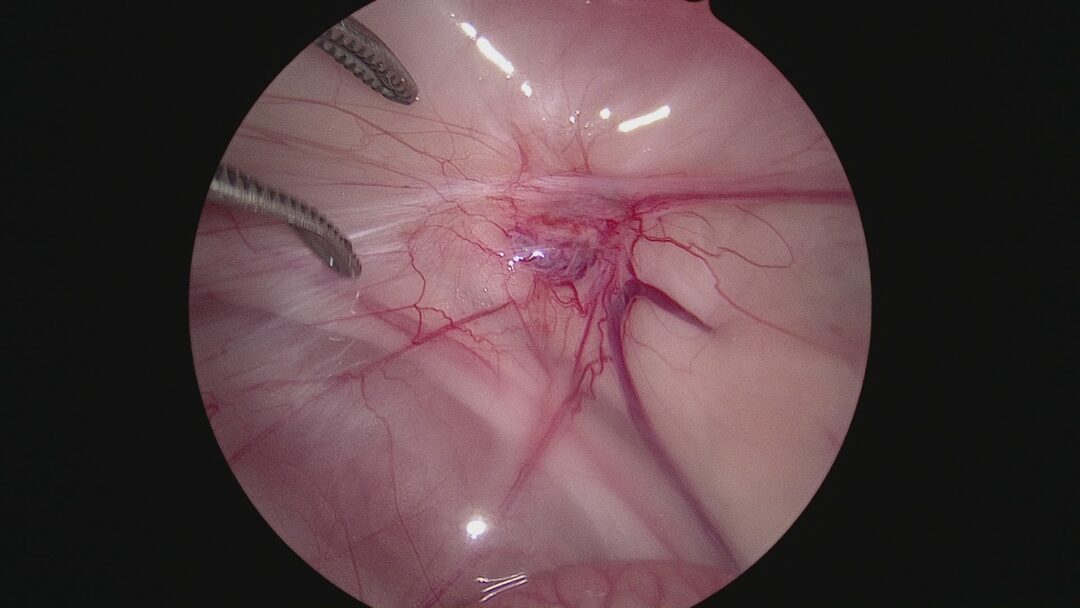

右側の卵巣も部分的に取り残しがある可能性があったので確認しましたが、明らかな卵巣は認められなかったので閉腹し終了としました。

私自身子宮単角症の猫ちゃんにお会いするのは初めてでしたが、指導医のもと腹腔鏡の視野の広さを生かし5mm3ヶ所の術創で手術が終了でき安心しました。卵巣遺残は開腹手術ではかなり大きく切皮しないと見つかり辛いことも経験していましたので腹腔鏡のメリットを再度確認できました。